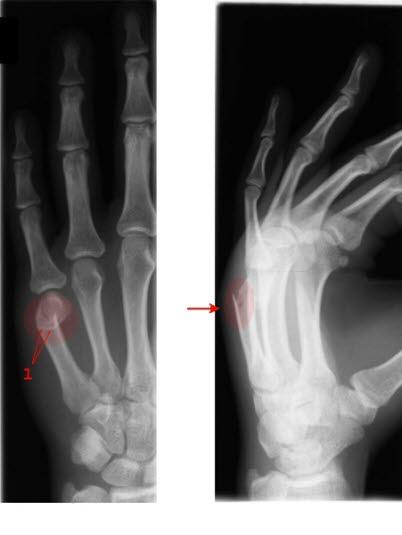

- Brudd i lillefingerens metakarp gjennom leddflaten mot CMC-leddet, betegnes omvendt Bennet-brudd

Etter forutgående skade blir hånden eller fingeren opphovnet og smertefull. Beinet kan ha blitt slått skjeivt, og diagnosen er da åpenbar. Et Bennet-brudd skyldes ofte et slag der tommelen tvinges bakover langs sin lengdeakse eller at den bøyes sterkt bakover (abduksjon). På samme måte oppstår et omvendt Bennet-brudd gjerne etter et slag der lillefingeren tvinges bakover langs sin lengdeakse eller at den bøyres sterkt bakover.

Ved Bennet-brudd er det hevelse og ømhet over 1. metakarp nær håndroten. Av og til er det tydelig feilstilling. Ved omvendt Bennet-brudd er det hevelse og ømhet over 5. metakarp på håndrotssiden.

Omvendt Bennet-brudd må også opereres fordi bruddet er ustabilt som følge av trekk og drag i senene. Vanligvis gjøres pinnefiksasjon (Kirschner-pinner) og deretter immobiliseres med gips i 6 uker. Etter at gipsen er fjernet, startes opptrening av håndfunksjonen.